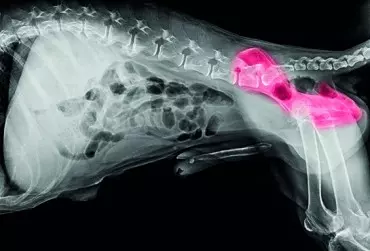

Zapalenia stawów u psów – CZĘŚĆ 2

Choroby zapalne stawów to skutek nie tylko pewnych nabytych schorzeń, ale także wrodzonych skłonności i nieprawidłowości. W drugiej części rozważań nad zapaleniami stawów u psów zostanie omówionych kilka innych schorzeń przebiegających z zapaleniem stawów, gdzie część z nich będzie wymagała interwencji na wczesnym etapie życia, kiedy to właściciel najczęściej nie spodziewa się konieczności podejmowania decyzji o operacji pupila. Cechą wspólną niżej omówionych schorzeń – oprócz wywoływania procesów zapalnych w stawie – jest to, iż nieodpowiednio, zbyt późno lub w ogóle nieleczone mogą i najprawdopodobniej będą prowadzić do osteoartrozy, czyli choroby zwyrodnieniowej stawów.